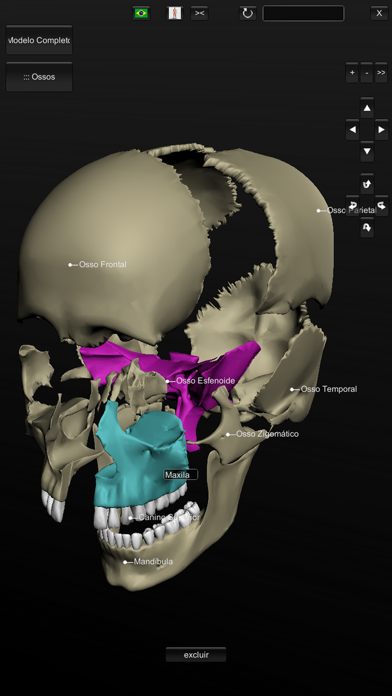

Explore a anatomia do corpo humano em todos os ângulos, de uma forma tridimensional e interativa. O aplicativo permite visualizar um modelo masculino* em 3D com todos os sistemas. (* o modelo feminino contido nesta versão inclui apenas o esqueleto e sistema reprodutor.) Em Português, Inglês, Espanhol e Latim (de acordo com a Terminologia Anatômica de 1998) - Novos comandos de toque: arraste 1 dedo para mostrar as legendas, 2 dedos para rotacionar o modelo, e 3 dedos para movê-lo -Agora com Realidade Aumentada (para IPhone6s ou superior) Este aplicativo foi projetado como um recurso adicional para o aprendizado de anatomia e não deve ser utilizado como fonte única de informação. Sistema incluídos: - esqueleto - musculatura contendo a origem e inserção - sistema nervoso - sistema circulatório (venoso e arterial) - sistema respiratório - ligamentos, cartilagens e articulações - sistema digestório - sistema urinário - sistema reprodutor - sistema linfático